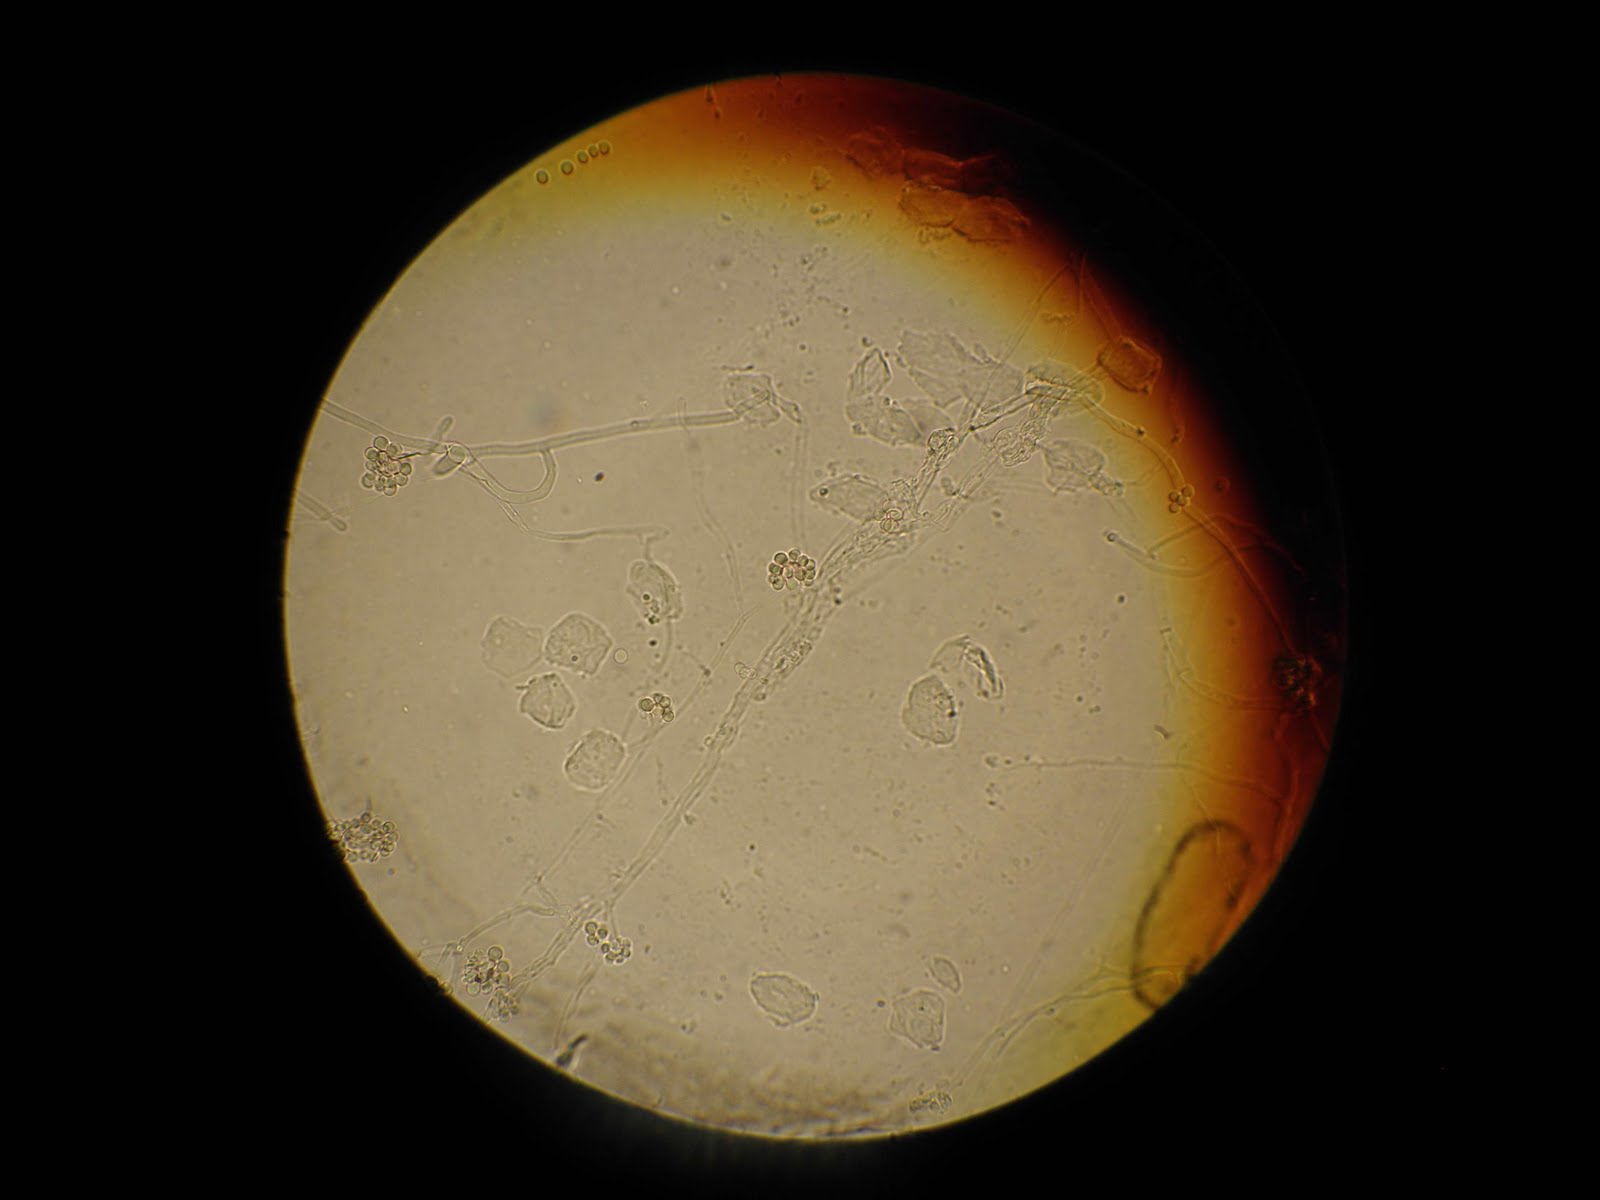

CUNNINGHAMELLA BERTHOLLETIAE (caso clinico nº2)